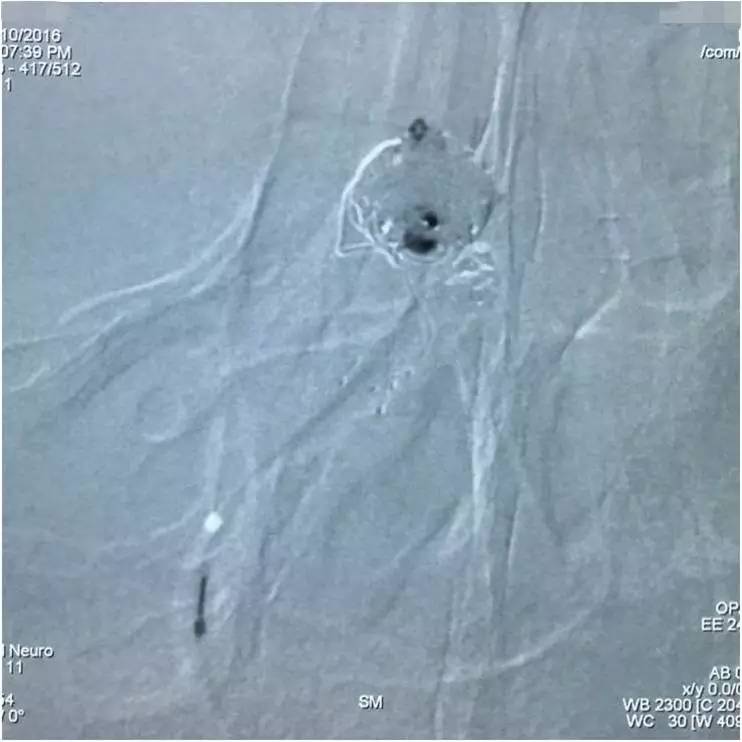

造影剂到底是从哪里漏进子瘤的呢?已经填塞到这种程度了,大造影是定位不了漏洞了,那就微量造影找吧!既然微导管从瘤腔的左后部填塞没达到消灭子瘤的目的,那么,反其道而行之,毅然撤出微导管,从支架网眼穿入瘤腔的右前部,看看漏洞是不是在此处?

▼影像资料

▼微量造影侧位显示子瘤显影。

▼空白路图填圈,惊喜地发现圈进入子瘤了,这是侧位空白路图。

▼这是正位空白路图,充分显示了双C臂的优势。

▼乘胜追击,子瘤被完全填满,这是侧位蒙片。

▼这是正位蒙片,子瘤被填塞,术者心里才踏实。

下面是术后各个角度的左椎动脉造影,可见基底动脉顶端动脉瘤和左小脑上动脉瘤完全栓塞,载瘤动脉畅通。基底动脉顶端动脉瘤的子瘤终于被消灭。

▼术后左椎动脉造影正位反汤28度。

▼纯正位。

▼侧位。

▼正位汤46度。